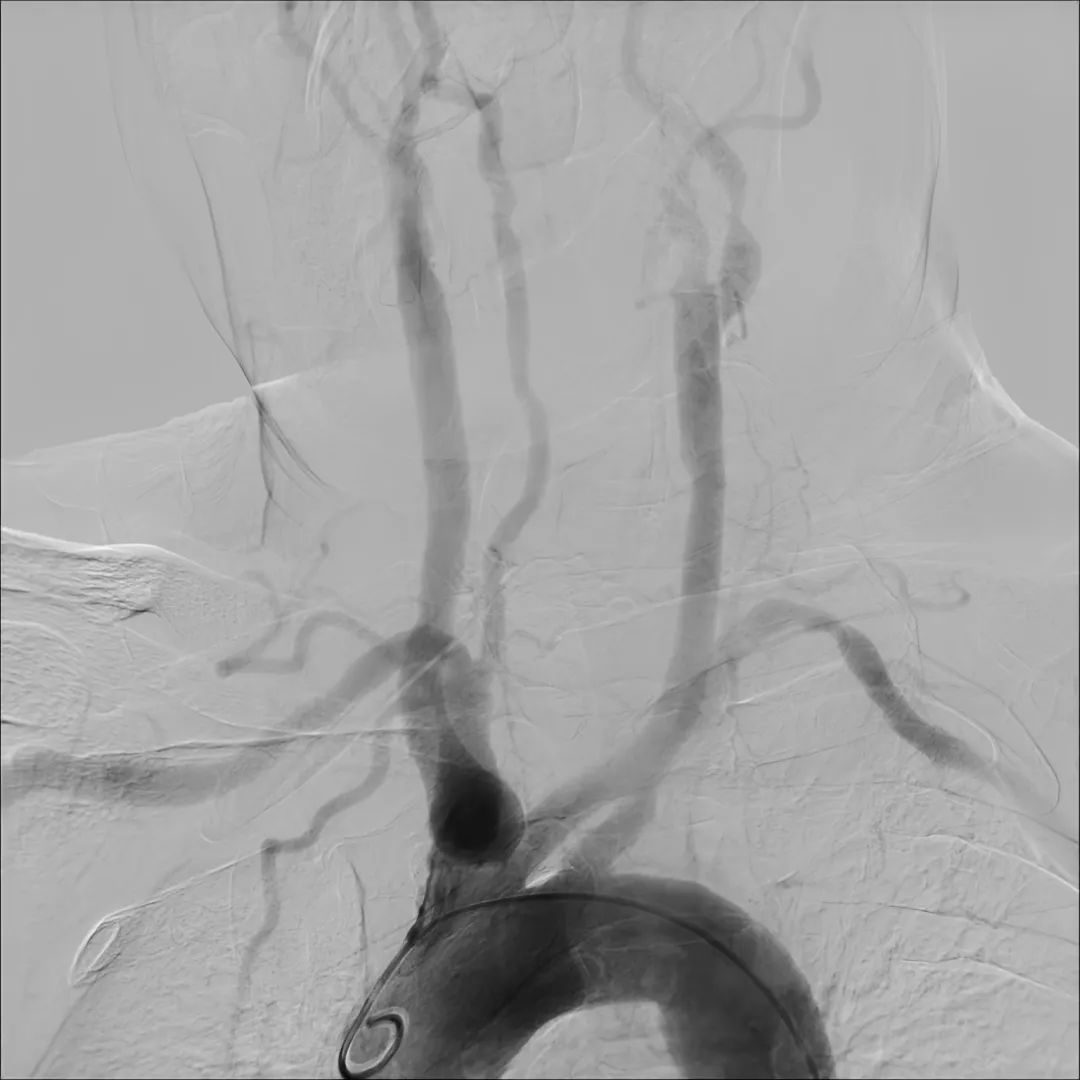

目前,唯邁醫(yī)療的DSA已裝機(jī)眾多三甲醫(yī)院,而剛剛完成裝機(jī)的濟(jì)南三院也在數(shù)日內(nèi)完成幾十例介入手術(shù),涵蓋經(jīng)介入造影治療,外周血管造影治療,心臟造影支架置入,滿足臨床多科室使用。

神經(jīng)造影

心臟造影